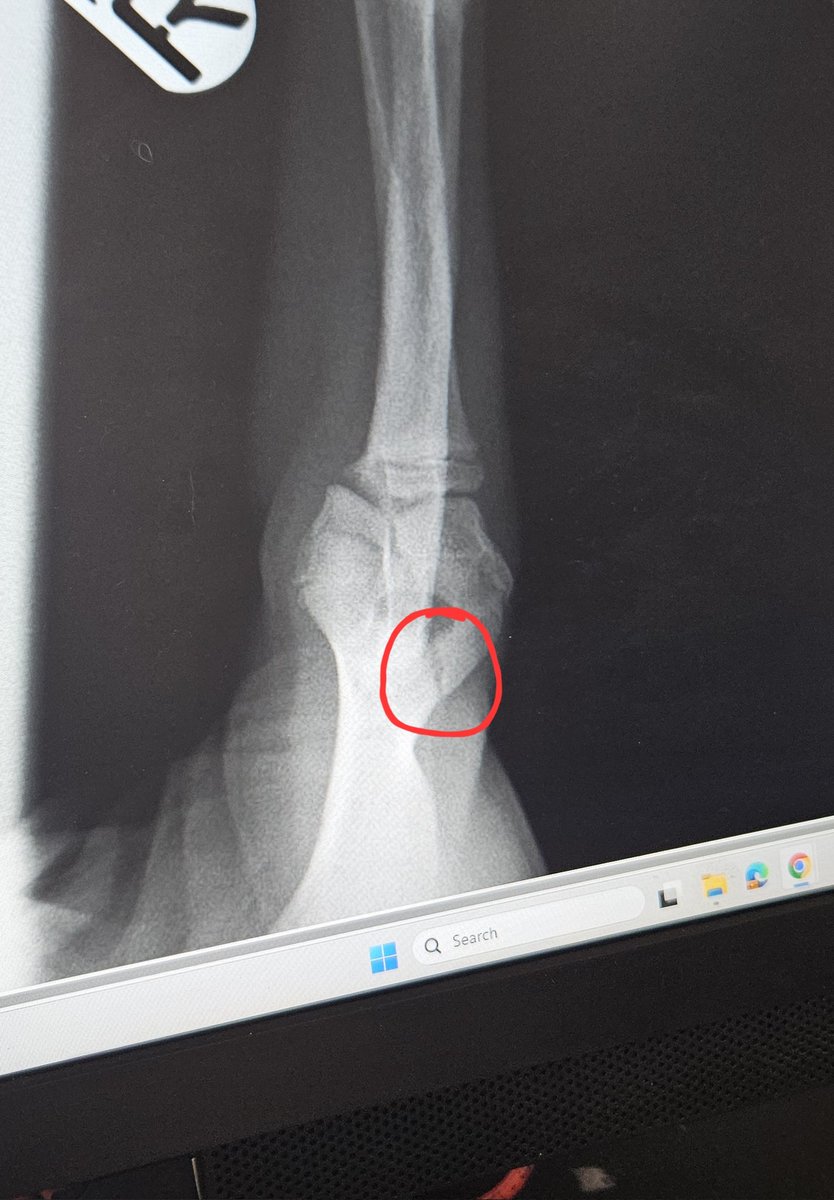

Sad update about our puppy's broken arm. Any shares or pennies would be hugely appreciated πŸ’”πŸΎ https://t.co/W8beuNZ3nD

Max has broken his front leg. He's on 4 weeks of bed rest, but if it doesn't start to heal we face it being amputated. It's cost us Β£840 so far for just xray and meds, with LOT more cost coming πŸ₯² I hate to ask for help, but all art coms are open: https://t.co/J5k6B27a9q

Max is currently in his amputation surgery and we're anxiously waiting on news. We need to pay minimum Β£1,100 when we pick him up later and any help would be immensely appreciated πŸ₯²πŸ§‘ https://t.co/Hs2nmNEOJE